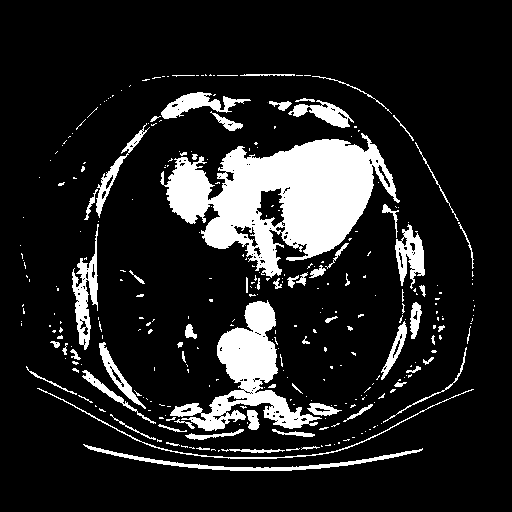

Reconstructed NATIVE CT scan (cycle consistency)

Full window (WL 1023.5, WW 4095 β†’ Low βˆ’1024, High +3071)

Actual HU range: [-1024.0, 3071.0]

Lung window (WL -600, WW 1500 β†’ Low βˆ’1350, High +150)

Actual HU range: [-1350.0, 150.0]

Mediastinum window (WL 40, WW 400 β†’ Low βˆ’160, High +240)

Actual HU range: [-160.0, 240.0]